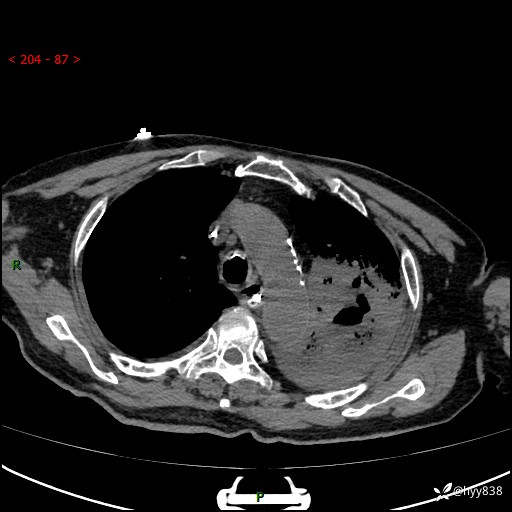

胸部CT平扫(2024.7.24)